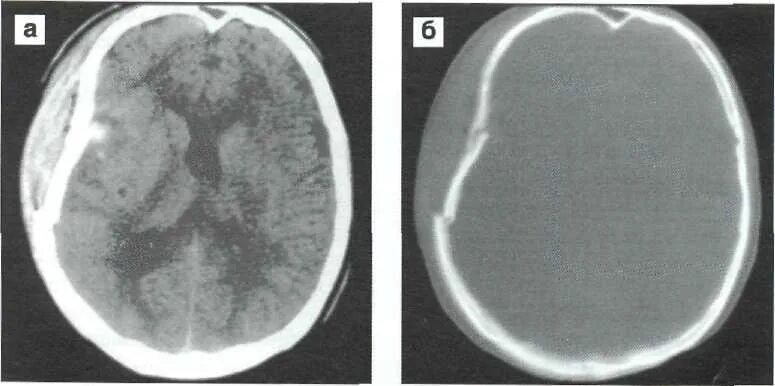

Оскольчатый перелом черепа